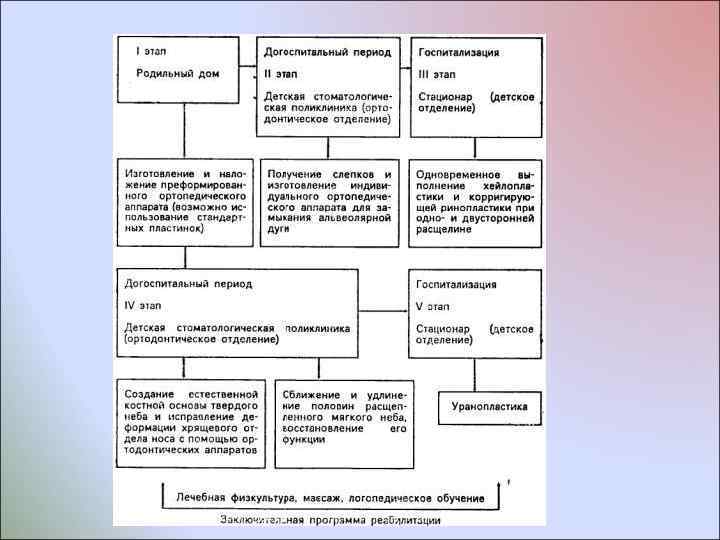

ОРТОПЕДИЧЕСКОЕ ЛЕЧЕНИЕ ДЕТЕЙ С РАСЩЕЛИНОЙ ГУБЫ И НЕБА В ПЕРИОДЕ НОВОРОЖДЕННОСТИ И В ГРУДНОМ ВОЗРАСТЕ В настоящее время благодаря созданию новых материалов и разработке более совершенных методов ортопедического лечения появилась возможность применить данный метод для лечения детей раннего возраста. Основными показаниями к применению ортопедической терапии у новорожденных и детей грудного возраста являются пороки развития лицевого черепа Дети, родившиеся с расщелиной губы, альвеолярного отростка, твердого и мягкого неба, с момента рождения должны находиться на диспансерном учете не только у педиатра, но и у стоматолога-ортопеда, поскольку они нуждаются в специальном ортопедическом лечении, которое должно быть начато до первого кормления. Раннее безотлагательное ортопедическое лечение этих детей в родильном доме позволяет нормализовать процесс вскармливания и выхаживания детей, предупредить возникновение вторичных деформаций, прогрессирующих с возрастом, для устранения которых требуется длительнее многоэтапное лечение

ОРТОПЕДИЧЕСКОЕ ЛЕЧЕНИЕ ДЕТЕЙ С РАСЩЕЛИНОЙ ГУБЫ И НЕБА В ПЕРИОДЕ НОВОРОЖДЕННОСТИ И В ГРУДНОМ ВОЗРАСТЕ В настоящее время благодаря созданию новых материалов и разработке более совершенных методов ортопедического лечения появилась возможность применить данный метод для лечения детей раннего возраста. Основными показаниями к применению ортопедической терапии у новорожденных и детей грудного возраста являются пороки развития лицевого черепа Дети, родившиеся с расщелиной губы, альвеолярного отростка, твердого и мягкого неба, с момента рождения должны находиться на диспансерном учете не только у педиатра, но и у стоматолога-ортопеда, поскольку они нуждаются в специальном ортопедическом лечении, которое должно быть начато до первого кормления. Раннее безотлагательное ортопедическое лечение этих детей в родильном доме позволяет нормализовать процесс вскармливания и выхаживания детей, предупредить возникновение вторичных деформаций, прогрессирующих с возрастом, для устранения которых требуется длительнее многоэтапное лечение

БЕЗОТЛАГАТЕЛЬНАЯ ОРТОПЕДИЧЕСКАЯ ПОМОЩЬ ДЕТЯМ С РАСЩЕЛИНОЙ ГУБЫ, АЛЬВЕОЛЯРНОГО ОТРОСТКА, ТВЕРДОГО И МЯГКОГО НЕБА В РОДИЛЬНОМ ДОМЕ Специализированная помощь ребенку, родившемуся с расщелиной губы и неба, должна быть организована по принципу неотложной. С этой целью необходимо создать специальную бригаду врачей, которая по сигналу из родильных домов, отделений городских больниц и медико-санитарных частей может выезжать для оказания помощи новорожденному в первые часы после рождения, т. е. до первого кормления. В состав ригады должен входить врач-ортопед, медицинская сестра и зубной техник. Дети, родившиеся в родильных домах городов и районов области, с помощью санавиации могут быть доставлены в родильное отделение областной больницы. Выездная бригада должна быть оснащена специальным оборудованием (портативная бормашина, зубоврачебный и абразивный инструментарий, набор оттискных ложек, слепочная масса, средства для изготовления, обработки и полировки преформированного ортопедического аппарата). Оснащение бригады может обеспечиваться ортодонтическим отделением базовой поликлиники, а стерильный материал и антисептические растворы предоставляются родильным отделением на месте. Специализированная бригада по показаниям направляет детей из родильного дома в детское стационарное отделение стоматологической клиники.

БЕЗОТЛАГАТЕЛЬНАЯ ОРТОПЕДИЧЕСКАЯ ПОМОЩЬ ДЕТЯМ С РАСЩЕЛИНОЙ ГУБЫ, АЛЬВЕОЛЯРНОГО ОТРОСТКА, ТВЕРДОГО И МЯГКОГО НЕБА В РОДИЛЬНОМ ДОМЕ Специализированная помощь ребенку, родившемуся с расщелиной губы и неба, должна быть организована по принципу неотложной. С этой целью необходимо создать специальную бригаду врачей, которая по сигналу из родильных домов, отделений городских больниц и медико-санитарных частей может выезжать для оказания помощи новорожденному в первые часы после рождения, т. е. до первого кормления. В состав ригады должен входить врач-ортопед, медицинская сестра и зубной техник. Дети, родившиеся в родильных домах городов и районов области, с помощью санавиации могут быть доставлены в родильное отделение областной больницы. Выездная бригада должна быть оснащена специальным оборудованием (портативная бормашина, зубоврачебный и абразивный инструментарий, набор оттискных ложек, слепочная масса, средства для изготовления, обработки и полировки преформированного ортопедического аппарата). Оснащение бригады может обеспечиваться ортодонтическим отделением базовой поликлиники, а стерильный материал и антисептические растворы предоставляются родильным отделением на месте. Специализированная бригада по показаниям направляет детей из родильного дома в детское стационарное отделение стоматологической клиники.

В родильном доме в первые часы после рождения ребенок обеспечивается ортопедическим аппаратом —преформированной пластинкой, которая не только разобщает носовую и ротовую полости, но и стимулирует рост недоразвитых и слаборазвитых фрагментов верхней челюсти, изменяя их положение. После осмотра и обследования новорожденного в присутствии неонатолога, соблюдая правила асептики с помощьюэластичной массы и специальной ложки получают оттиск с верхней челюсти. Методика получения слепка такова: тщательно приготовляют оттискную массу, которую накладывают на хорошо подобранную ложку с отводным каналом. С целью предупреждения асфиксии необходимо вызвать громкий плач ребенка путем пальцевого давления на пяточную кость. Во время плача ложку с оттискной массой вводят в полость рта ребенка и накладывают на область альвеолярных отростков справа и слева. При этом вначале надавливают пальцем на дистальный отдел ложки, в результате чего оттискная масса перемещается кпереди, под фрагменты верхней губы и через отводной канал в полость рта.

В родильном доме в первые часы после рождения ребенок обеспечивается ортопедическим аппаратом —преформированной пластинкой, которая не только разобщает носовую и ротовую полости, но и стимулирует рост недоразвитых и слаборазвитых фрагментов верхней челюсти, изменяя их положение. После осмотра и обследования новорожденного в присутствии неонатолога, соблюдая правила асептики с помощьюэластичной массы и специальной ложки получают оттиск с верхней челюсти. Методика получения слепка такова: тщательно приготовляют оттискную массу, которую накладывают на хорошо подобранную ложку с отводным каналом. С целью предупреждения асфиксии необходимо вызвать громкий плач ребенка путем пальцевого давления на пяточную кость. Во время плача ложку с оттискной массой вводят в полость рта ребенка и накладывают на область альвеолярных отростков справа и слева. При этом вначале надавливают пальцем на дистальный отдел ложки, в результате чего оттискная масса перемещается кпереди, под фрагменты верхней губы и через отводной канал в полость рта.

Плач ребенка должен продолжаться до затвердевания оттискной массы, когда она теряет свою текучесть, вследствие чего устраняется угроза попадания гранул оттискной массы в дыхательные пути и пищеварительный тракт. Вывести оттиск из полости рта ребенка несложно. Оттиск, как правило, выводится одним конгломератом. На нем должны быть точно отображены контуры альвеолярных и небных отростков правой и левой половин верхней челюсти, хорошо контурироваться их вестибулярные границы, размеры, характер и протяженность расщелины, а также средний отдел твердого и мягкого неба. Рельеф оттиска зависит от характера расщелины. Затем отливают гипсовую модель и проводят ее преформацию в трех взаимно перпендикулярных плоскостях.

Плач ребенка должен продолжаться до затвердевания оттискной массы, когда она теряет свою текучесть, вследствие чего устраняется угроза попадания гранул оттискной массы в дыхательные пути и пищеварительный тракт. Вывести оттиск из полости рта ребенка несложно. Оттиск, как правило, выводится одним конгломератом. На нем должны быть точно отображены контуры альвеолярных и небных отростков правой и левой половин верхней челюсти, хорошо контурироваться их вестибулярные границы, размеры, характер и протяженность расщелины, а также средний отдел твердого и мягкого неба. Рельеф оттиска зависит от характера расщелины. Затем отливают гипсовую модель и проводят ее преформацию в трех взаимно перпендикулярных плоскостях.

Сегменты преформированной модели соединяются между собой посредством пластинки, которую изготовляют из любого базисного материала. В переднем отделе ортопедического аппарата по проекции расщелины вваривают металлическую фиксирующую петлю из ортодонтической проволоки диаметром 0, 6 мм. Полимеризацию преформированного ортопедического аппарата проводят в специальной кювете под давлением. Затем осуществляют шлифовку и полировку аппарата. Готовый аппарат вводят в полость рта ребенка, контролируют его границы и степень прилегания к альвеолярным отросткам верхней челюсти, после чего аппарат фиксируют к эластичной давящей повязке посредством полосок лейкопластыря, проведенных через металлическую петлю. Введенный в полость рта ортопедический аппарат вызывает у младенца раздражение слизистой оболочки, и у него появляются первые сосательные движения. Медицинский персонал родильного отделения приготавливает 10 г сцеженного молока и проводит первое кормление ребенка с помощью соски и аппарата. Активность сосания повышается с каждой минутой, и к концу кормления ребенок сосет ровно и спокойно. Медицинский персонал родильного отделения и мать получают инструкции о режиме пользования преформированным ортопедическим аппаратом и правилах туалета полости рта.

Сегменты преформированной модели соединяются между собой посредством пластинки, которую изготовляют из любого базисного материала. В переднем отделе ортопедического аппарата по проекции расщелины вваривают металлическую фиксирующую петлю из ортодонтической проволоки диаметром 0, 6 мм. Полимеризацию преформированного ортопедического аппарата проводят в специальной кювете под давлением. Затем осуществляют шлифовку и полировку аппарата. Готовый аппарат вводят в полость рта ребенка, контролируют его границы и степень прилегания к альвеолярным отросткам верхней челюсти, после чего аппарат фиксируют к эластичной давящей повязке посредством полосок лейкопластыря, проведенных через металлическую петлю. Введенный в полость рта ортопедический аппарат вызывает у младенца раздражение слизистой оболочки, и у него появляются первые сосательные движения. Медицинский персонал родильного отделения приготавливает 10 г сцеженного молока и проводит первое кормление ребенка с помощью соски и аппарата. Активность сосания повышается с каждой минутой, и к концу кормления ребенок сосет ровно и спокойно. Медицинский персонал родильного отделения и мать получают инструкции о режиме пользования преформированным ортопедическим аппаратом и правилах туалета полости рта.

При каждом сосательном и глотательном движении возникает функциональная нагрузка, передаваемая через преформированный аппарат на неправильно расположенные и недоразвитые фрагменты верхней челюсти, в результате чего нормализуется их топография и стимулируется рост. Мы рекомендуем пользоваться аппаратом постоянно в течение суток, за исключением времени, отведенного для туалета полости рта. Аппарат не беспокоит ребенка. Он к нему быстро привыкает, о чем свидетельствует отказ от сосания без аппарата.

При каждом сосательном и глотательном движении возникает функциональная нагрузка, передаваемая через преформированный аппарат на неправильно расположенные и недоразвитые фрагменты верхней челюсти, в результате чего нормализуется их топография и стимулируется рост. Мы рекомендуем пользоваться аппаратом постоянно в течение суток, за исключением времени, отведенного для туалета полости рта. Аппарат не беспокоит ребенка. Он к нему быстро привыкает, о чем свидетельствует отказ от сосания без аппарата.

Применение стандартизованных преформированных ортопедических аппаратов у детей с пороками развития лицевого черепа в родильном доме до первого кормления позволяет: 1) оказать безотлагательную ортопедическую помощь новорожденному; 2) оказать неотложную ортопедическую помощь новорожденному в любом родильном отделении той местности, где нет ортодонта или ортопеда, владеющего методикой ортопедического лечения новорожденных с пороками развития лицевого черепа; 3) стабилизировать процесс развития вторичных деформаций и предотвратить дальнейшее увеличение дефекта в области альвеолярного отростка и неба; 4) нормализовать процесс вскармливания и обеспечить полноценное физическое развитие ребенка; 5) разобщить полости рта и носа, что позволит предотвратить развитие вторичных деформаций не только органов полости рта, но и полости носа;

Применение стандартизованных преформированных ортопедических аппаратов у детей с пороками развития лицевого черепа в родильном доме до первого кормления позволяет: 1) оказать безотлагательную ортопедическую помощь новорожденному; 2) оказать неотложную ортопедическую помощь новорожденному в любом родильном отделении той местности, где нет ортодонта или ортопеда, владеющего методикой ортопедического лечения новорожденных с пороками развития лицевого черепа; 3) стабилизировать процесс развития вторичных деформаций и предотвратить дальнейшее увеличение дефекта в области альвеолярного отростка и неба; 4) нормализовать процесс вскармливания и обеспечить полноценное физическое развитие ребенка; 5) разобщить полости рта и носа, что позволит предотвратить развитие вторичных деформаций не только органов полости рта, но и полости носа;

6) использовать акт сосания и глотания в качестве лечебного фактора путем направления силы мышечного воздействия через аппарат на исправление положения костных фрагментов верхней челюсти и устранение дефекта в области альвеолярного отростка, а также перевода сквозной расщелины в несквозную; 7) начать раннее ортопедическое лечение детей, использовав для этого эластичность тканей, которые легко преформируются в нужном направлении под действием ортопедического аппарата; 8) уменьшить продолжительность ортопедического лечения, направленного на реконструкцию верхней челюсти, и создать благоприятные условия для своевременного проведения хейло- и уранопластики, исключив при этом натяжение мягких тканей и костные рассечения; 9) завершить реабилитацию детей с такого рода патологией в преддошкольном возрасте и обеспечить им нормальное обучение с первого класса в общеобразовательной школе, в связи с чем отпадает необходимость в содержании школ-интернатов для таких детей, что даст большой экономический эффект; 10) обеспечить хорошее физическое развитие ребенка, начиная с первых дней после рождения, о чем свидетельствуют ежемесячное увеличение массы тела и хорошее общее состояние (новорожденные, пользующиеся преформированными ортопедическими аппаратами, реже болеют острыми респираторными заболе-ваниями, чем дети, которым не было проведено раннее ортопедическое лечение).

6) использовать акт сосания и глотания в качестве лечебного фактора путем направления силы мышечного воздействия через аппарат на исправление положения костных фрагментов верхней челюсти и устранение дефекта в области альвеолярного отростка, а также перевода сквозной расщелины в несквозную; 7) начать раннее ортопедическое лечение детей, использовав для этого эластичность тканей, которые легко преформируются в нужном направлении под действием ортопедического аппарата; 8) уменьшить продолжительность ортопедического лечения, направленного на реконструкцию верхней челюсти, и создать благоприятные условия для своевременного проведения хейло- и уранопластики, исключив при этом натяжение мягких тканей и костные рассечения; 9) завершить реабилитацию детей с такого рода патологией в преддошкольном возрасте и обеспечить им нормальное обучение с первого класса в общеобразовательной школе, в связи с чем отпадает необходимость в содержании школ-интернатов для таких детей, что даст большой экономический эффект; 10) обеспечить хорошее физическое развитие ребенка, начиная с первых дней после рождения, о чем свидетельствуют ежемесячное увеличение массы тела и хорошее общее состояние (новорожденные, пользующиеся преформированными ортопедическими аппаратами, реже болеют острыми респираторными заболе-ваниями, чем дети, которым не было проведено раннее ортопедическое лечение).